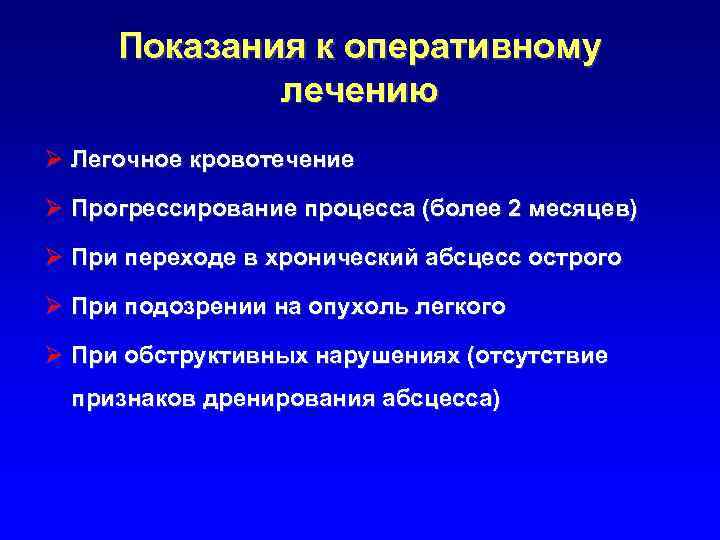

Показания к оперативному лечению Ø Легочное кровотечение Ø Прогрессирование процесса (более 2 месяцев) Ø При переходе в хронический абсцесс острого Ø При подозрении на опухоль легкого Ø При обструктивных нарушениях (отсутствие признаков дренирования абсцесса)